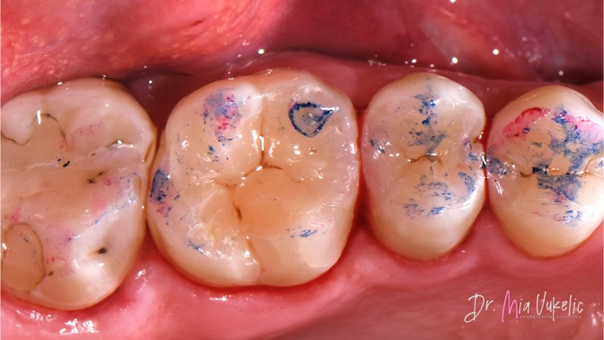

Zur Vorbereitung des Schmelzes für die Adhäsion wurde eine selektiven Ätztechnik gewählt und ein Ätzgel mit 35 % Phosphorsäure (Ultra-Etch™ Ätzgel, Ultradent Products) 15 Sekunden aufgetragen.

Nach dem Abspülen mit Wasser (30 Sekunden) wurde das Zwei-Komponenten-Adhäsivsystem (Clearfil™ SE Bond, Kuraray*) verwendet. Zunächst wurde der Primer aufgetragen, anschließend das Bonding. Die Polymerisation wurde mit einer kabellosen VALO™ LED-Polymerisationsleuchte (Ultradent Products) durchgeführt.